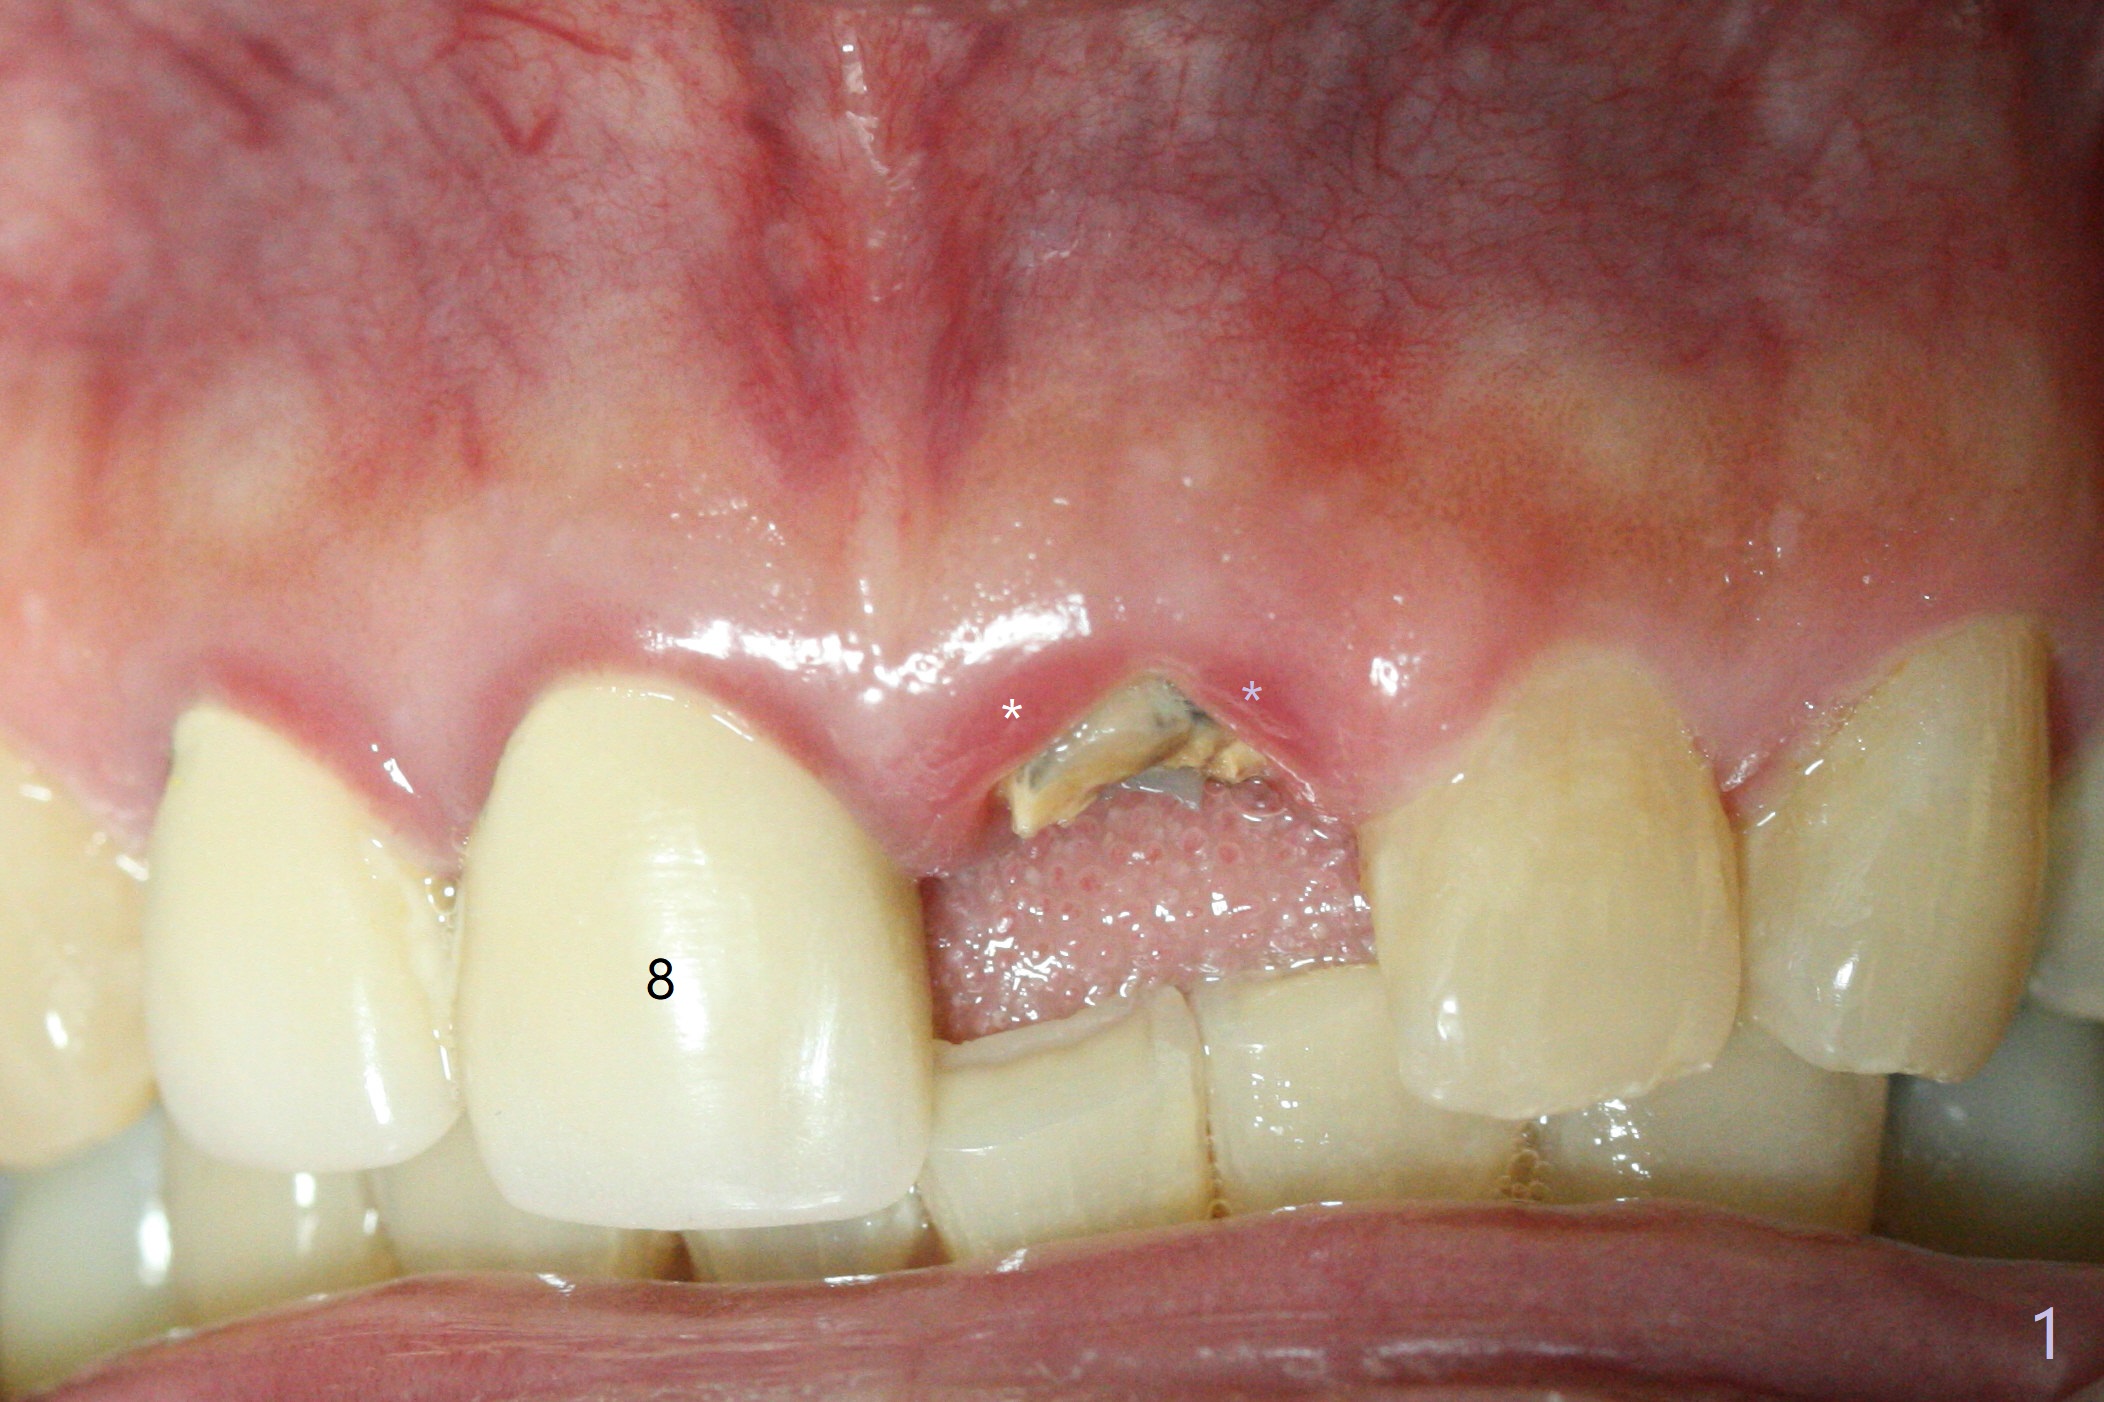

A 58-year-old man fractures the tooth #9 equigingival (Fig.1) and fiber post (Fig.2,3 *). The marginal gingiva is erythematous and edematous (Fig.1 *), suggesting biologic width violation. Redo crown would aggravate the issue. In addition, the mesiobuccal root of the tooth #14 has vertical fracture (Fig.4,5), evidence of heavy mastication. In fact the tooth #13 was also fractured apparently due to heavy occlusion before extraction. It is the best to extract the tooth #9 for implant (Fig.6), or tissue-level (3.5x14 or 17 mm).